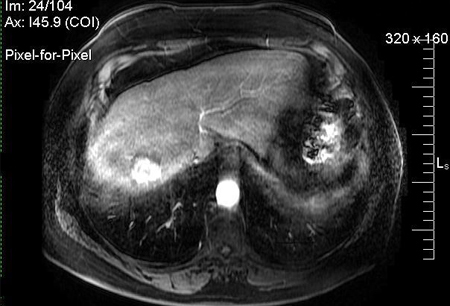

- contrast MRI of abdomen